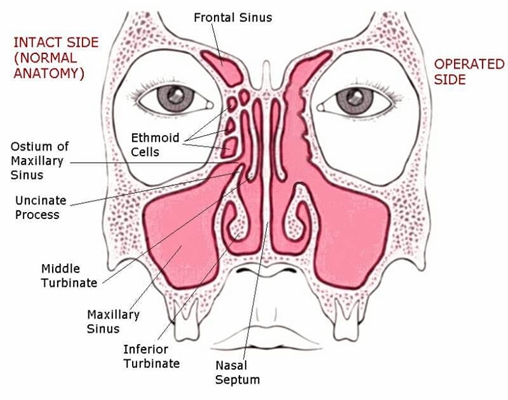

鼻中隔偏曲圖片

鼻中隔彎曲手術圖解 (44)

鼻中隔彎曲手術圖解 (45)

鼻中隔彎曲手術圖解 (46)

鼻中隔彎曲手術圖解 (47)

鼻中隔彎曲手術圖解 (48)

鼻中隔彎曲手術圖解 (49)

鼻中隔彎曲手術圖解 (50)

鼻中隔彎曲手術圖解 (43)

鼻中隔彎曲手術圖解 (42)

鼻中隔彎曲手術圖解 (41)

鼻中隔彎曲手術圖解 (30)

鼻中隔彎曲手術圖解 (31)

鼻中隔彎曲手術圖解 (32)

鼻中隔彎曲手術圖解 (33)

鼻中隔彎曲手術圖解 (34)